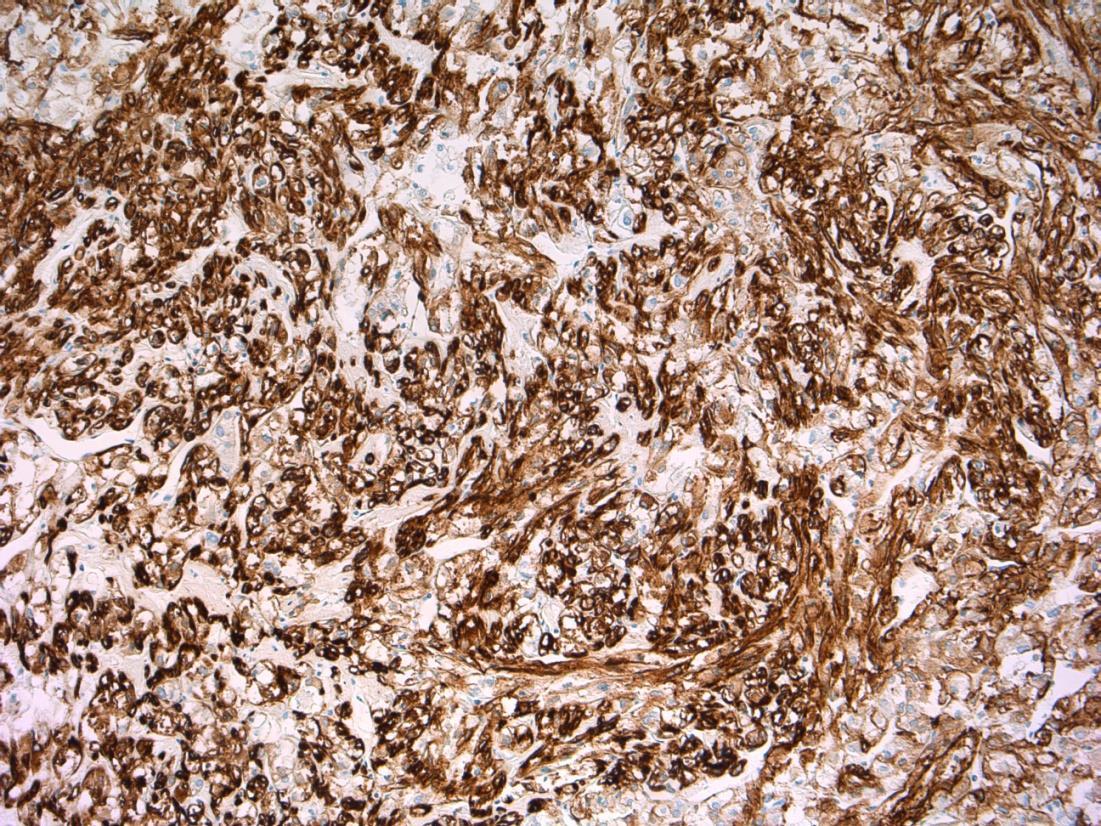

HMB45 CD117 AE1/3 SMA

Liver Description: Liver containing well circumscribed spindle cell tumour with 3 components – smooth muscle cells (predominant), adipose tissue and blood vessels. Diagnosis: angiomyolipoma Differential Diagnosis: Leiomyoma (usually no prominent vascular or adipose component, negative for HMB45) GIST (CD117+) Mets of sarcoma / spindle cell carcinoma – more atypia Plan: IHC: SMA+, HMB45+, CD117-, AE1/3+ Correlate with clinical history ? Tuberous sclerosis etc Comments: • Liver is 2nd commonest site after kidney • Often detected incidentally, usually benign • May be sporadic but is associated with tuberous

and with TSC2 / PKD1 contiguous gene

(especially if

AML

sclerosis

syndrome

bilateral/multifocal).